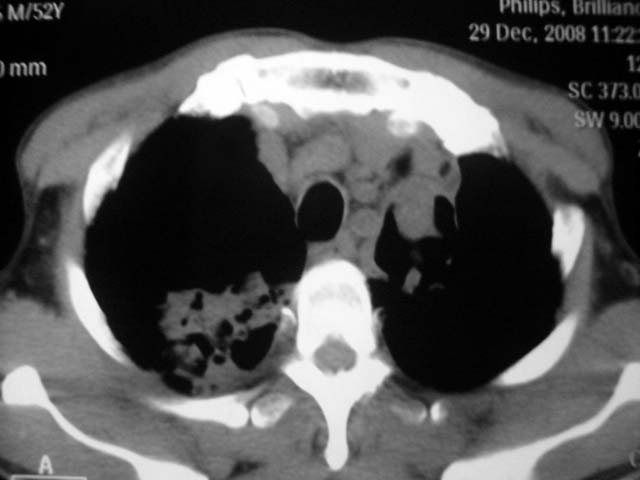

男,52岁,发热2月,糖尿病史。

抗结核治疗irpz方案,血糖未治疗,空腹15.9左右。症状无好转,左胸痛。

2、双肺见多发片状及结节状高密度影,大多数病灶中心均见“空泡征”。

3、纵隔内淋巴结肿大。

结果:两肺继发性肺结核并曲霉菌感染。